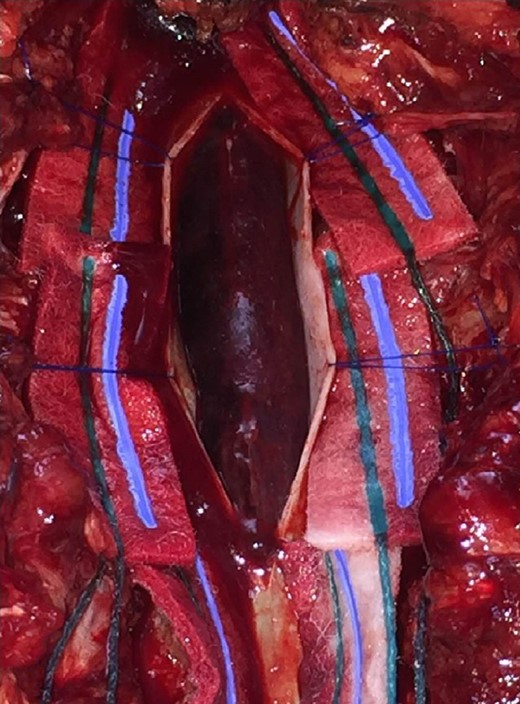

Patient is taken to the operating room immediately, where a wide laminectomy was performed from T4 to T7, durotomy and drainage of subdural hematoma (Figs 3 and 4). No complications during surgery.